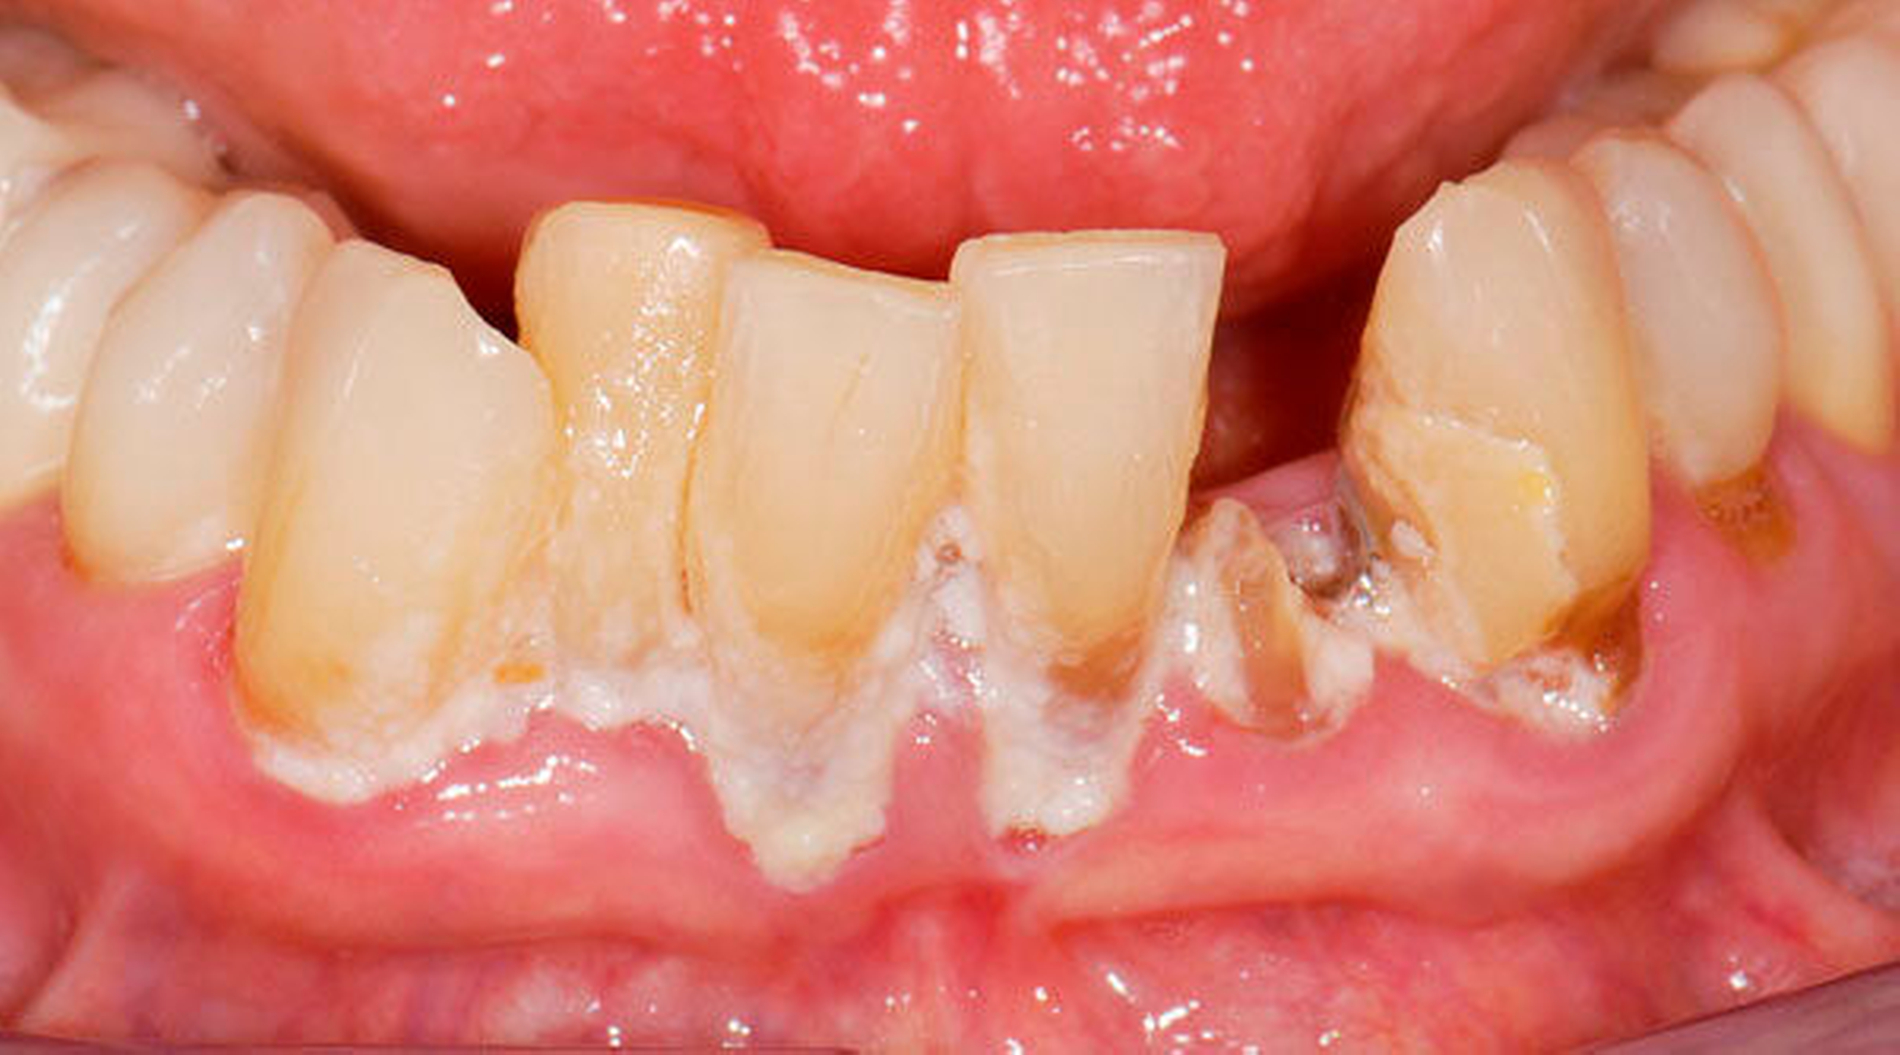

Bei älteren Patienten mit (infolge geistiger Einschränkung) vernachlässigter Mundhygiene, exemplarisch in Abbildung 5 dargestellt, wird zuweilen eine Extraktion sämtlicher Zähne vorgenommen. Eine anschließende prothetische Versorgung ist in solchen Fällen wegen mangelnder Adaptationsfähigkeit oftmals nicht mehr möglich. Dies hat zur Konsequenz, dass die Betroffenen in ihrem Aussehen, ihrer Sprachfunktion und ihrer Fähigkeit zur Nahrungsaufnahme noch eingeschränkter sind als vorher, verbunden mit vielerlei Nachteilen im psycho-sozialen Umfeld.

Abbildung 3: ausgedehnte Kronen- und Wurzelkaries unter einer Krone am Pfeilerzahn 47 einer seit Jahrzehnten eingegliederten Brücke von 45–47 bei einer 71-jährigen Patientin, die nach einer zerebrovaskulären Erkrankung unter Antikoagulantientherapie steht, vor etwa zwei Jahren hat sie eine Umstellung auf eine fluoridfreie Zahnpaste vorgenommen.

Wenn irgend möglich, sollte deshalb erwogen werden, einen Erhaltungsversuch wenigstens bei den gut zugänglichen Schneide- und Eckzähnen vorzunehmen, auch wenn die Prognose unsicher ist und Rezidive der Wurzelkaries zu erwarten sind. Die in Abbildung 5 gezeigte Patientin lebte zunächst noch zu Hause und wurde von einer Pflegeperson täglich betreut. Nach Umzug in ein Pflegeheim wird sie von ihrer ehemaligen Pflegerin nach wie vor ein- bis zweimal wöchentlich aufgesucht. Die Pflegerin nimmt bei ihr ein- bis zweimal wöchentlich eine Zahnreinigung mittels Zahnbürste und Interdentalraumbürsten vor, was mit einem Zeitaufwand von jeweils maximal fünf bis zehn Minuten verbunden ist. Obwohl sich nach zwei Jahren an einigen Zähnen ein Kariesrezidiv eingestellt hat, konnte der Zahnbestand gehalten werden.

Abbildung 4: Anliegen eines 76,5-jährigen Patienten (Anfrage per E-Mail). Zitat: „Mich plagt eine … Entzündung des Mundraums, die auch das Zahnfleisch meiner Zahnstummel angreift, weshalb ich nur noch Breiartiges zu essen vermag. Ein Angsthase wie ich geht zum Zahnarzt NUR unter dem Eindruck akuter Schmerzen!“

Damit wird die Hygienefähigkeit zumindest partiell verbessert und Spielraum für künftige Planungen und Vorgehensweisen unter besseren Bedingungen belassen. Das Procedere ist in den Abbildungen 4 und 5 beschrieben. Bei dem in Abbildung 4 vorgestellten Patienten lag eine Oralphobie im Seniorenalter vor. Die Verlaufsbeschreibung macht deutlich, dass selbst im fortgeschrittenen Alter eine Adaptation an zahnärztliche Interventionen im Einzelfall noch möglich ist.